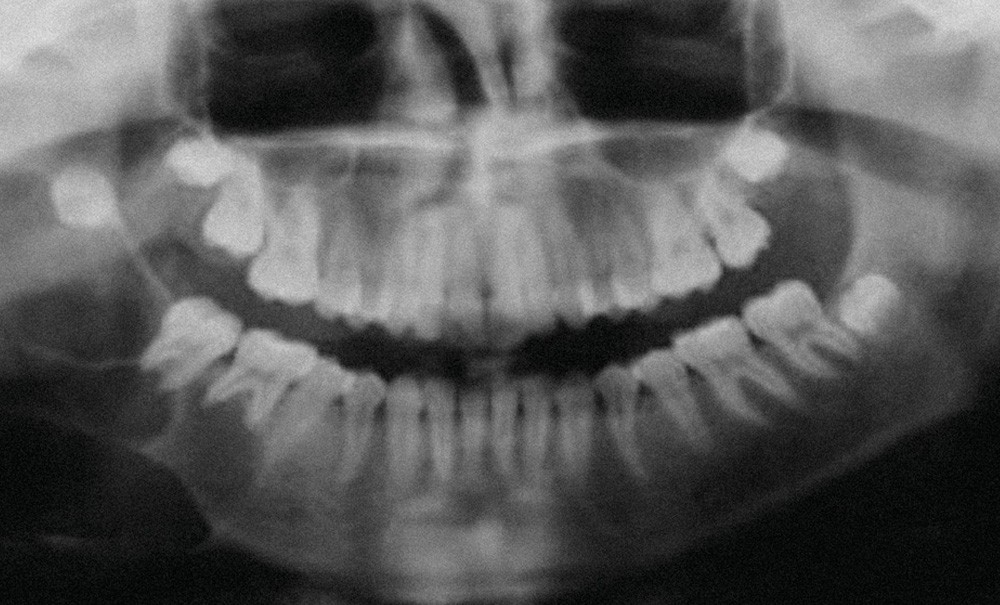

Radiologiquement, les aspects sont variés, mais la forme la plus caractéristique est une image radioclaire, bien limitée, avec un aspect en « bulle de savon ».